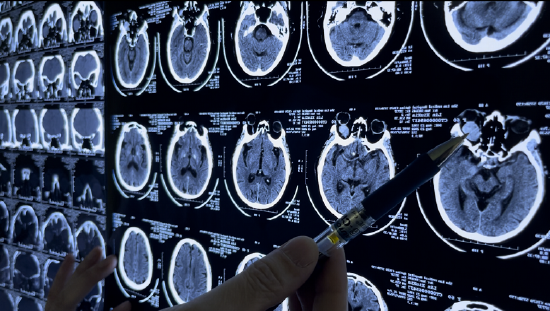

郭庆院长为冷大娘做了详尽检查,凭借多年临床经验和丰富的影像学知识,明确诊断为左眼眶海绵状血管瘤 。

由于冷大娘肿物范围大,病程长,肿物且与眼部多处组织紧密相连,要想把肿物完整切除而不影响颜面部外观和眼部功能,难度极大。但如果不治疗,则可能继续发展进而压迫视神经,造成视力、视野丧失——风险高是冷大娘求医上门重要原因!

郭庆教授及团队仔细评估,精心设计了手术方案——采用微创技术摘除肿瘤,在结膜下切开一个1.5公分左右的切口,绕过眼球下方,向眶深部分离,暴露出肿瘤后,用组织钳夹住肿瘤,从周围的神经、肌肉、脂肪等组织中将肿瘤精准分离,手术时程仅耗时10多分钟,郭院长带领手术团队牛晓霞主任以及助手顾然医生、郑晓雨医生,凭借精湛的技术和丰富的经验顺利分离并完整切除肿物。(体积20×28×23mm,而正常成人眼球前后径约为24mm,可见手术难度)

手术时间短,并不意味着手术难度小。郭院长介绍,眶内组织有多条神经、血管、肌肉结构极其复杂。肿瘤长在眼球正后方,这让手术操作的空间非常狭窄,切除肿瘤时无法将肿瘤全部暴露在视野内,分离肿瘤只能凭借多年的经验和感觉。更加危险的是,肿瘤体积较大,已经挤压了视神经,并和视神经紧紧贴在一起,一旦手术操作失误,就会伤及视神经,影响术后视力,甚至致盲。